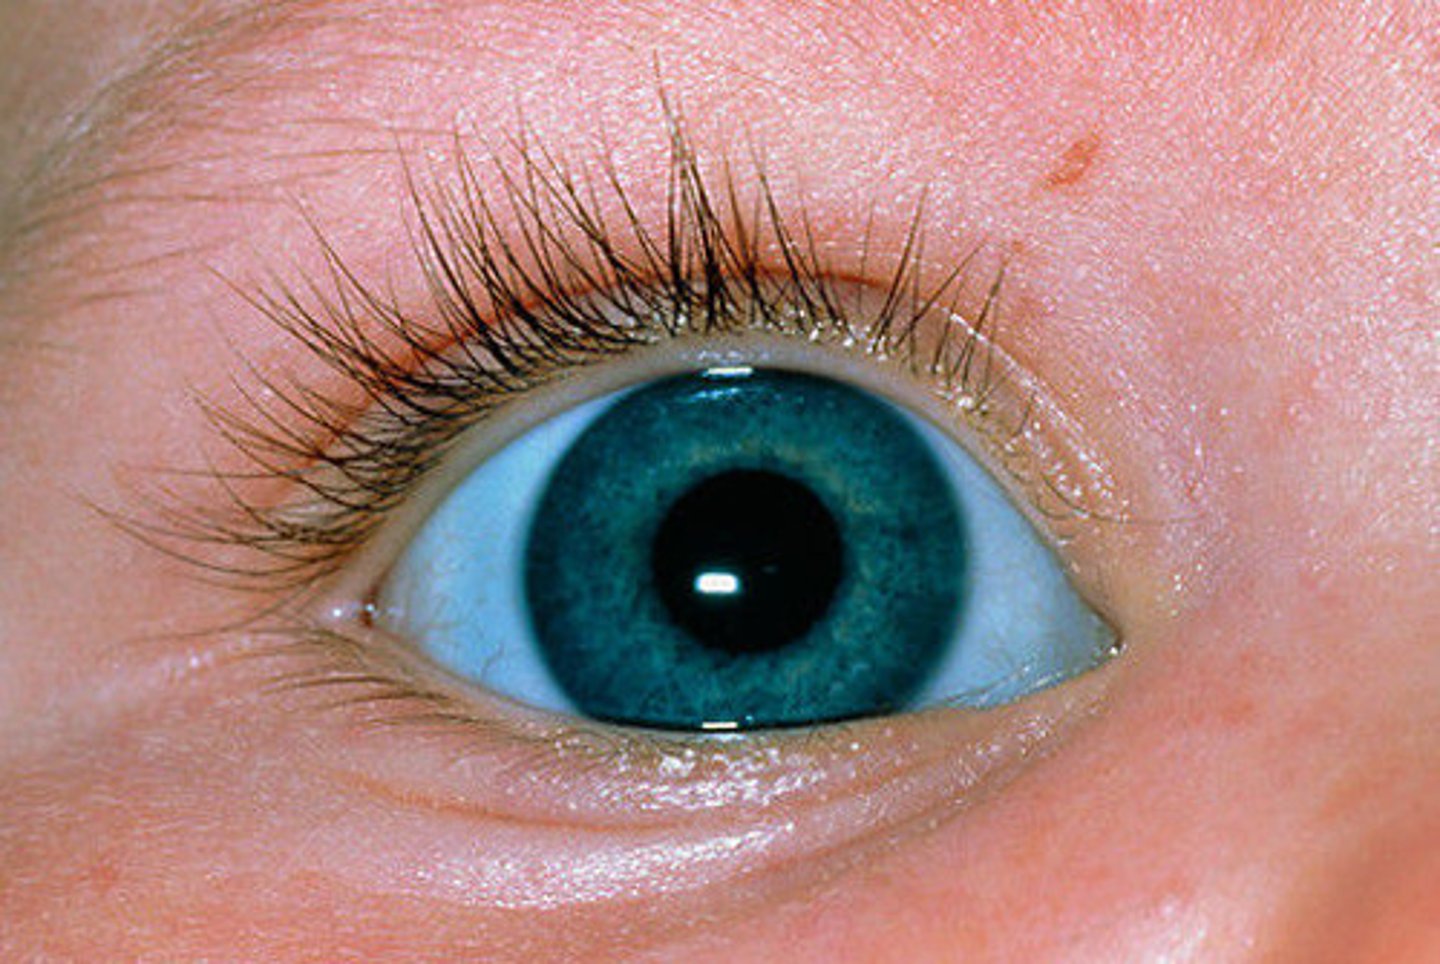

Blue sclera

Osteogenesis Imperfecta (Type I collagen defect forming triple helix)

Blue due to exposure of choroidal veins